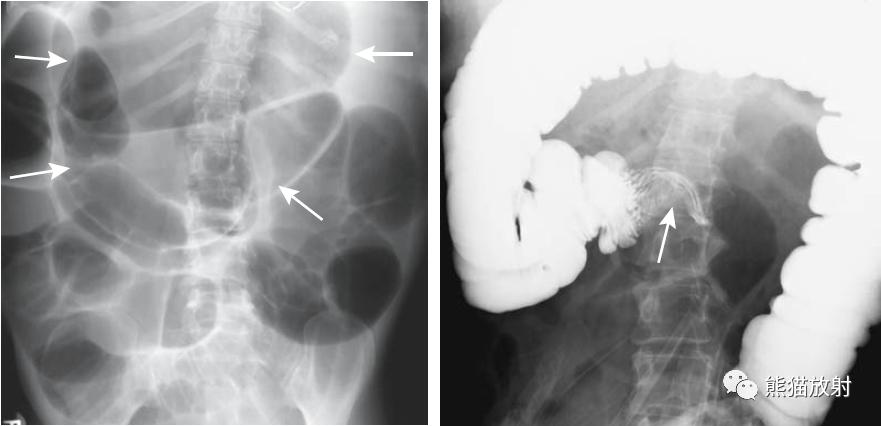

盲肠肠扭转。 盲肠明显扩张并移位至左侧(箭头)。右腹部可见小肠扩张,提示继发小肠梗阻。

盲肠扭转。X线摄片显示中腹部肠管明显扩张(箭头)。钡餐检查示升结肠扭曲部位可见特征性的鸟嘴征(箭头)。